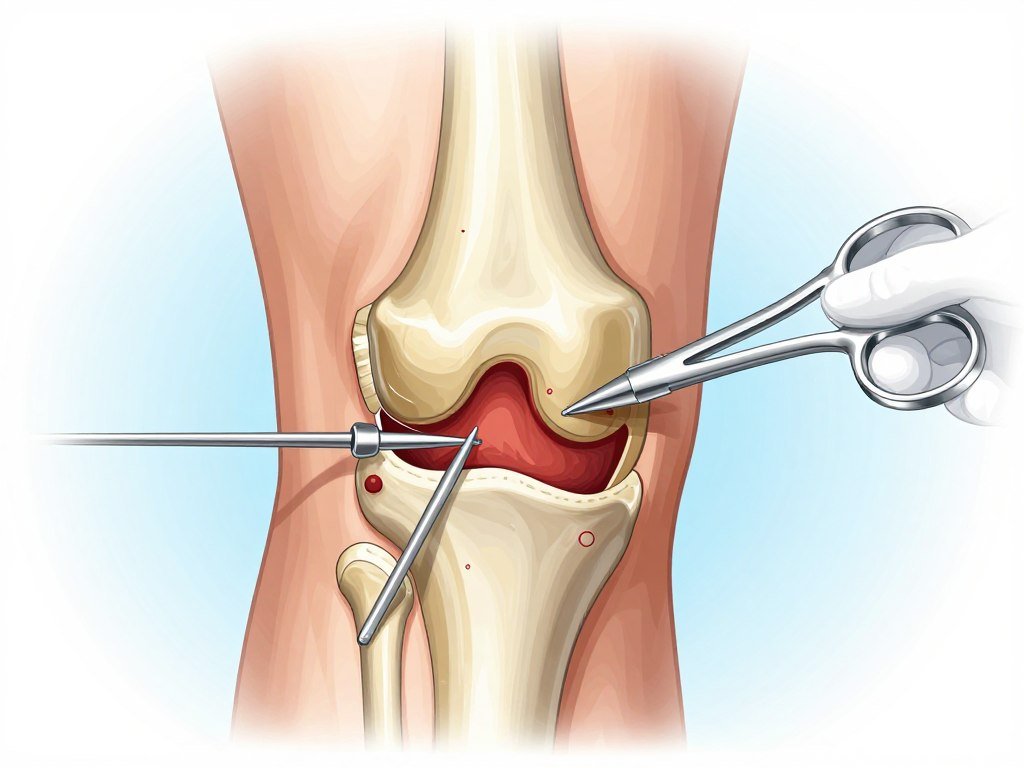

Surgical Options (Last Resort)

- Arthroscopy: Minimally invasive procedure to repair torn cartilage or ligaments.

- Partial Knee Replacement: Replaces only the damaged portion of the knee.

- Total Knee Replacement: Replaces the entire knee joint with an artificial joint.